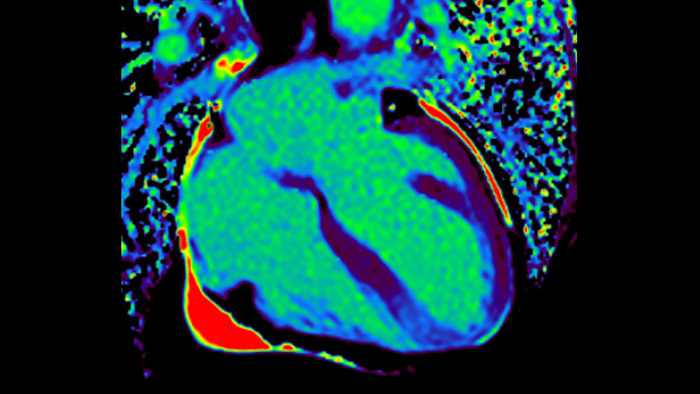

Diagnostic and prognostic utility of cardiac MR is increasing. Assess the anatomy and function of the heart using cine acquisitions, acquire information about perfusion and viability of the cardiac tissue, visualise potential edema with black blood sequence, access and even quantify tissue characterisation with CardiacQuant.

IntelliSpace Portal MR Caas5,6 Strain7 assists in patient diagnosis and monitoring by providing global strain parameters such as global longitudinal strain (GLS), global circumferential strain (GCS), and global radial strain (GRS), using short and long axis MR images, as well as describing the myocardium deformation- such as shortening, thickening, and lengthening during the cardiac cycle.